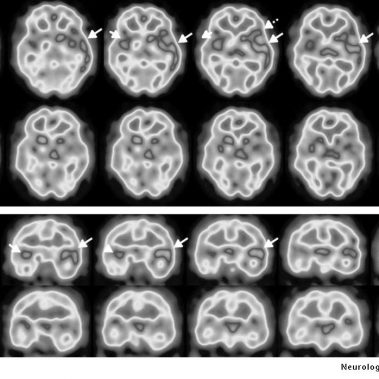

Cenedyt Servicio de Medicina Nuclear se creó hace más de 20 años. Las técnicas de imagen han tenido un desarrollo espectacular en los últimos años y cada vez juegan un papel más relevante en el proceso diagnóstico y terapéutico de los pacientes. El número de exploraciones realizadas es cada vez más elevado.

Estamos especializados en Medicina Nuclear y Densitometría. Nuestro objetivo y ofrecer al paciente la máxima calidad en Diagnóstico y tratamiento, basándonos en nuestra amplia experiencia y últimas tecnologías.